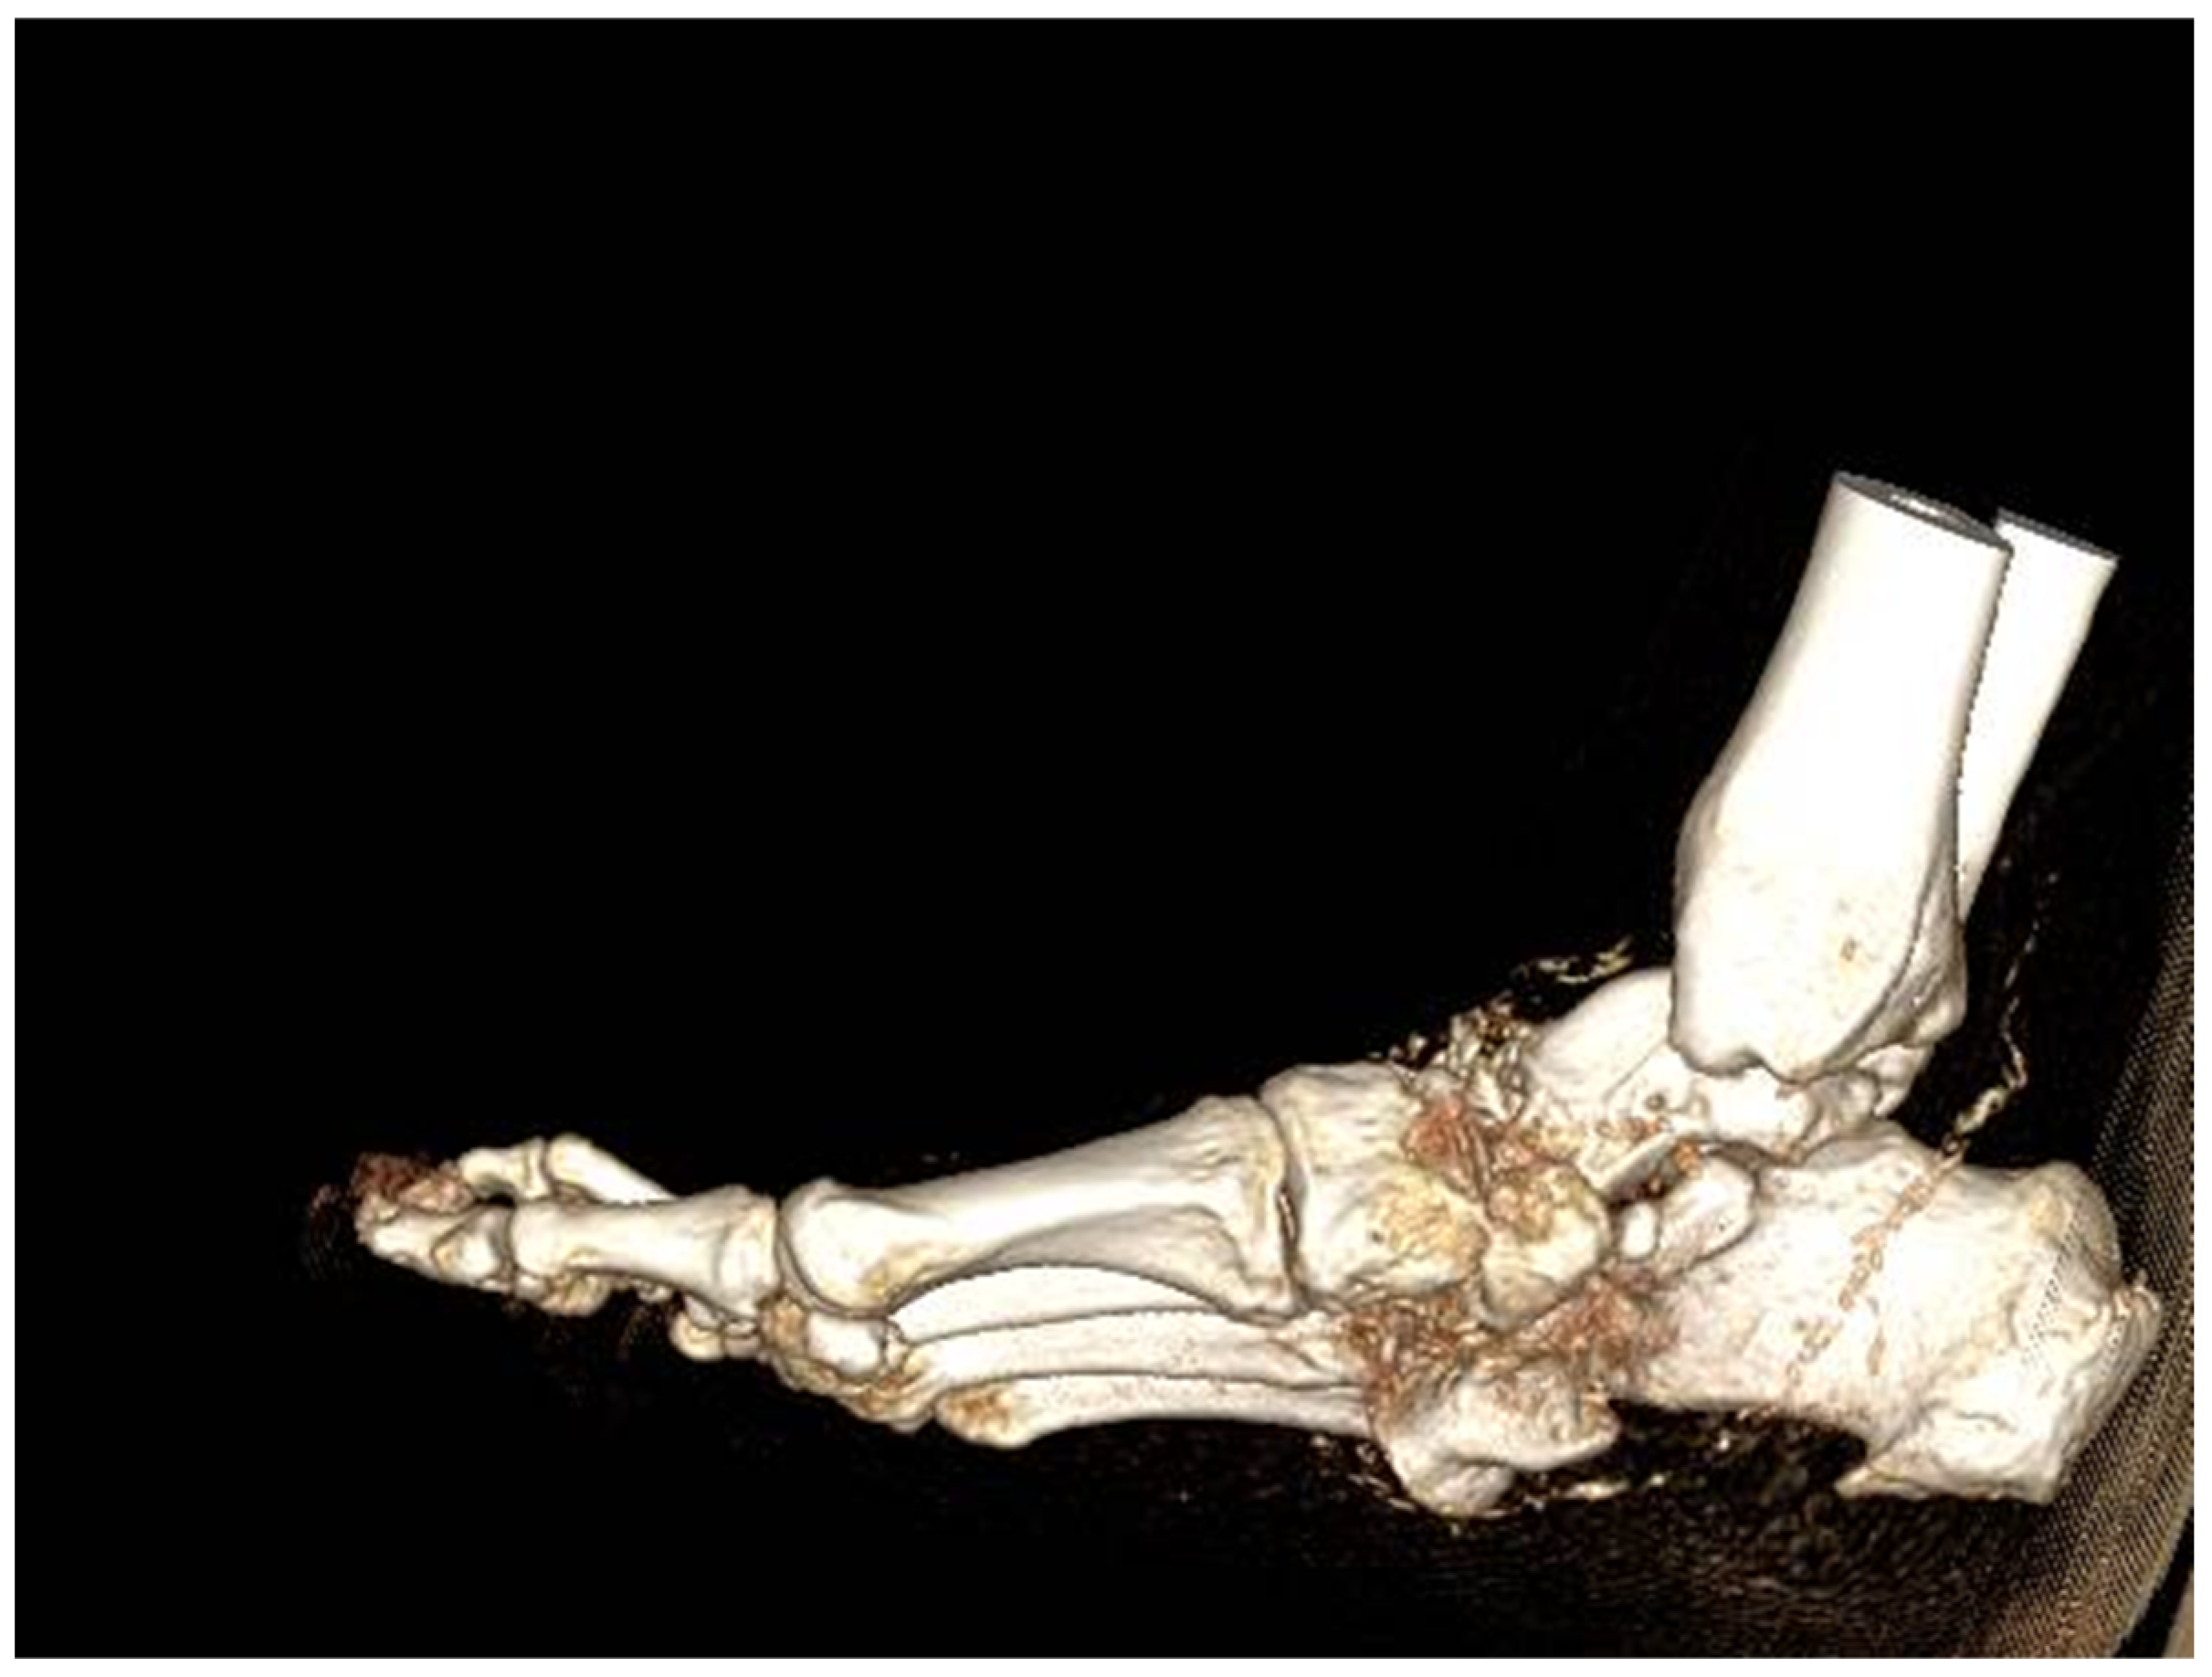

5. Computed Tomography Scan